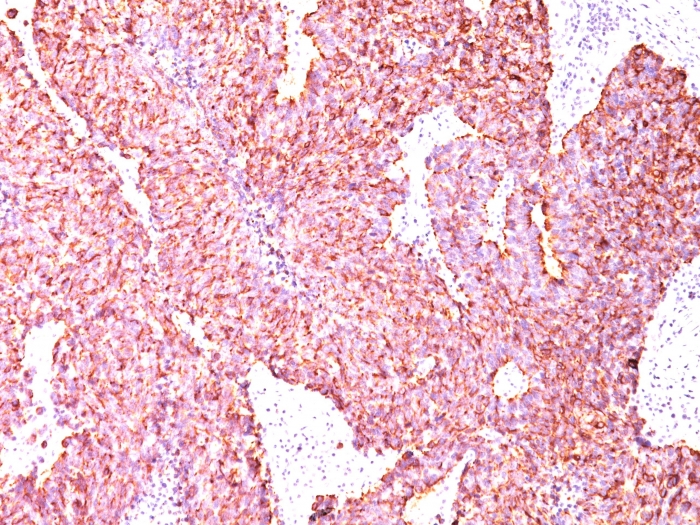

Formalin-fixed, paraffin-embedded human Pancreas stained with Chromogranin A Mouse Monoclonal Antibody (CGA/414).

Chromogranin A is present in neuroendocrine cells throughout the body, including the neuroendocrine cells of the large and small intestine, adrenal medulla and pancreatic islets. It is an excellent marker for carcinoid tumors, pheochromocytomas, paragangliomas, and other neuroendocrine tumors. Co-expression of chromogranin A and neuron specific enolase (NSE) is common in neuroendocrine neoplasms. Reportedly, co-expression of certain keratins and chromogranin indicates neuroendocrine lineage. The presence of strong anti-chromogranin staining and absence of anti-keratin staining should raise the possibility of paraganglioma. The co-expression of chromogranin and NSE is typical of neuroendocrine neoplasms. Most pituitary adenomas and prolactinomas readily express chromogranin.